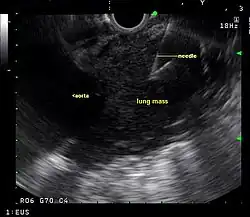

Endoscopic ultrasound (EUS) is an endoscopic technique where a miniaturized ultrasound probe is passed through the mouth into the upper gastrointestinal tract to investigate organs and structures close to the esophagus, stomach, or duodenum, such as the lung. In 1993, Wiersema published the first description of EUS to diagnose and stage lung cancer,[31] done by advancing a fine needle through the esophagus into adjacent lymph nodes. Numerous subsequent studies have shown this general methodology to be effective, very safe, minimally invasive, and very well tolerated. Given these advantages, many authorities think that EUS together with endobronchial ultrasound (EBUS) enhances lung cancer diagnosis and staging.[32]

Endoscopic ultrasound (EUS)

A metaanalysis published in 2007, based on 1,201 cancers in 18 high-quality clinical trials carefully selected by predefined criteria from the literature, systematically examined the performance of EUS-guided FNA in NSCLC staging. Two scenarios were considered: the setting of enlarged lymph nodes on CT (suggestive but not diagnostic of cancer), and the obverse scenario of an absence of lymph node enlargement on CT (suggestive but not diagnostic of no cancer).[28] Overall, in both settings, minor complications were reported in 0.8% of procedures; no major complications were recorded. EUS-FNA in enlarged discrete mediastinal lymph nodes had an excellent pooled sensitivity (8 studies) of 90% (95% CI, 84 to 94%) and specificity of 97% (95% CI, 95 to 98%). EUS-FNA in the setting of no enlarged mediastinal lymph nodes on CT had a pooled sensitivity (4 studies) of 58% (95% CI, 39 to 75%) and specificity of 98% (95% CI, 96 to 99%). Although this sensitivity (58% in CT-negative disease) might on first consideration seem disappointing, if EUS is performed as a staging test it can help avoid more invasive staging procedures, or surgery, if positive (for the presence of cancer). In other words, an EUS that has a positive result (shows cancer) will avoid further needless surgery, whereas a result not showing cancer may be false-negative, and probably requires an excisional biopsy technique for confirmation, such as VATS or mediastinoscopy.

EUS can reliably reach the lymph node stations 5, 7, 8 and 9. In the superior mediastinum the trachea is somewhat to the right of the esophagus which makes it often possible to reach left-sided area 2 and 4 lymph nodes and, less often, right sided paratracheal lymph nodes.[33] In general, EUS is most appropriate for evaluation of the posterior inferior mediastinum while mediastinoscopy or EBUS are best for the anterior superior mediastinum. The feasibility of EUS-FNA of aorto-pulmonary space (subaortic) lymph nodes (station 5) is a major advantage of EUS. Evaluation of this station has traditionally required a paramedian mediastinotomy (Chamberlain procedure). EUS can easily sample celiac lymph nodes, which cannot be reached by the other mediastinal staging methods. In one recent study an unexpectedly high incidence of celiac lymph node metastasis (11%) was noted.[34] EUS can also be used to biopsy potential left adrenal metastases, whereas the right adrenal gland is mostly inaccessible.[35]